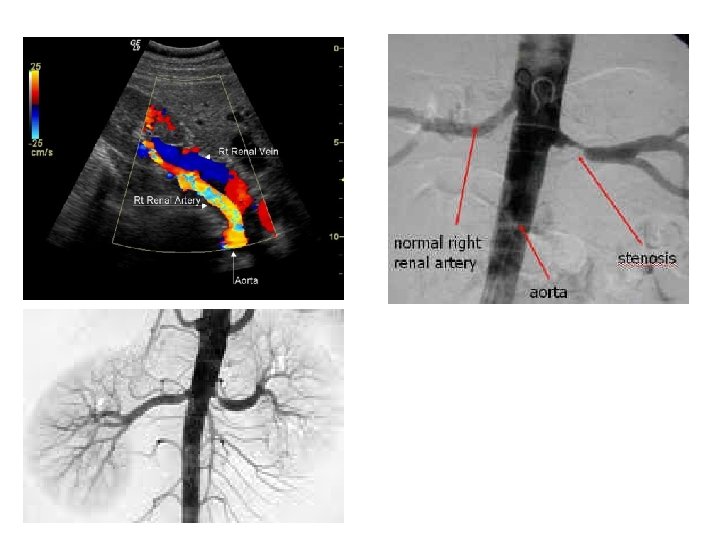

MÉTODOS Si existe experiencia técnica disponible, la ecografía Doppler puede ser suficiente como prueba de screening no invasiva. La sensibilidad del pico sistólico es del 85% y la especificidad del 92%. La TAC helicoidal tiene una sensibilidad del 98% y una especificidad del 94%.

VELOCIDAD SISTÓLICA PICO (VSP), útil para ERV TIEMPO DE ACELERACIÓN (tiempo que tarda en llegar al PICO SISTÓLICO temprano), INDICE DE RESISTENCIA (IR = VSP- VDP)/ VSP) De éstas, el IR sea probablemente el parámetro mejor estudiado. El IR es una función de la compliance renal y prerenal, FC, y resistencia vascular; Por lo que un cambio en el RI puede resultar de múltiples factores.

Las formas de las ondas de la arteria renal principal x el Doppler espectral deberían demostrar un patrón típico de órgano macizo con bajas resistencias parenquimatosas (IR 0. 7) y una VSP de hasta 200 cm/s. A nivel interlobar las arterias deberían mostrar una subida rápida con un tiempo breve de aceleración (<70 a 120 ms) y un RI entre 0. 5 y 0. 7. < 200 cm/seg) RI: 0. 5 -0. 7 RI: 0. 7

Si los vasos necesitan ser visualizados, la angiografía con RMN con gadolinio era preferida a la TAC helicoidal con iodo (al evitar la exposición al medio de radiocontraste) y a la arteriografía (porque además evita el riesgo de ateroembolismo). Sin embargo, la administración de gadolinio se asocia fuertemente a fibrosis sistémica nefrogénica, sobre todo en pacientes con enfermedad renal crónica estadíos 3 a 5 (Clearance de creatinina < 60 ml/min), más aún en diabéticos. El gadolinio está contraindicado en sujetos con Clearance de creatinina < 30 ml/’ A la fecha, la opinión de expertos difiere sobre el uso del gadolinio en pacientes con clearance de creatinina entre 30 y 60 ml/’.